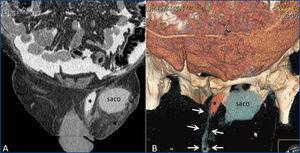

Varón de 76 años afecto de ERC estadio 4 secundaria a poliquistosis hepatorrenal con antecedente de hipertensión arterial de larga evolución, diabetes mellitus tipo 2, hiperuricemia, dislipemia y enfermedad pulmonar obstructiva crónica. Ante la situación de ERC avanzada y tras explicar las diferentes técnicas dialíticas, se inserta catéter peritoneal recto no autoposicionante de 1 cuff mediante cirugía abierta sin incidencias inmediatas y con buen funcionamiento durante el período de entrenamiento. Al mes de colocación del catéter, se inicia diálisis peritoneal continua ambulatoria (DPCA) en domicilio con pauta de 3 intercambios de 2 litros de dextrosa 1,5 %, inicialmente con balances neutros o negativos de 200-300 ml. A los 4 días de inicio del tratamiento en domicilio, acude a la Unidad de Diálisis Peritoneal refiriendo cuadro de edema genital, sin otra clínica asociada. Tras efectuarse ecografía testicular, se descarta patología a dicho nivel. Ante sospecha de fuga, se efectúa una tomografía axial computarizada (TAC)-peritoneografía, tras la administración (por el catéter) de 100 ml de contraste iodado hipoosmolar (Optiray® 300 mg/ml), confirmándose el paso de material de contraste peritoneal a través del cordón espermático hasta el escroto por presencia de un proceso peritoneovaginal permeable, aunque no dilatado (figura 1). Igualmente, también se aprecia la existencia de una hernia inguinal indirecta izquierda ipsilateral con un saco de hasta 58 mm de diámetro (figura 2). Ante estos hallazgos, se decide realizar reposo peritoneal y se indica cirugía para corrección de la hernia inguinal y cierre del conducto peritoneovaginal. Con estas medidas, y tras reiniciar diálisis peritoneal con volúmenes bajos, un mes después de la reintervención no se objetivó nueva fuga.

Figura 1. Peritoneografía por tomografía computarizada

Figura 2. Peritoneografía por tomografía computarizada